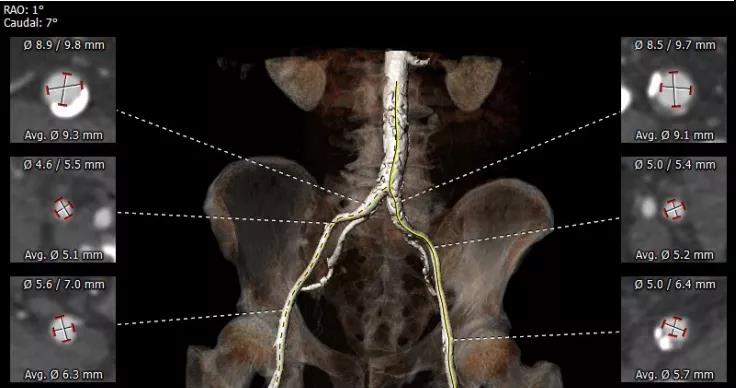

主动脉瓣瓣环 瓦氏窦

重度肺气肿、多发肺大泡 股动脉入路评估

患者男性,66岁,活动后胸闷气促3年,近1年内反复昏厥2次。术前心脏超声提示先天性二叶式主动脉瓣畸形伴重度狭窄、轻度反流,峰值流速4.4m/s,峰值压差89mmHg,平均跨瓣压差57mmHg,瓣口面积0.7cm2,同时心功能差,EF仅30%。CT评估显示主动脉瓣为Type I型二叶瓣,重度钙化,瓣环面积460.4mm2,测算直径24.2mm。左冠脉开口高度14.2mm,右冠脉开口高度13.7mm。患者合并重度肺气肿、多发性肺大泡,且心功能差,STS评分为3.2%,经多学科专家讨论,认为该患者不适合常规开胸外科手术,符合TAVI入组标准。

术前经详尽影像学重建、评估及病例讨论,选择右侧股动脉为主入路,跨瓣成功后21#球囊预扩张,再“0位”植入23# Renatus球扩式介入主动脉瓣。手术耗时约1小时,患者全程生命体征平稳,出血极少。介入主动脉瓣功能表现出色,主动脉瓣峰值流速及平均跨瓣压差分别降至2.2m/s和10mmHg,轻度瓣周漏,无瓣中反流,未发生传导阻滞与冠脉异常。